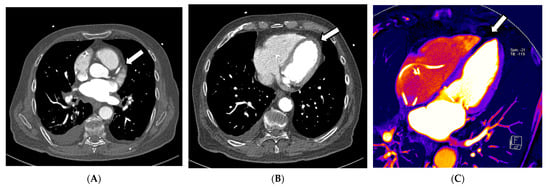

In this context, in addition to common CCTA, additional information on myocardial perfusion imaging (MPI), and thus, the functionality and prognosis of myocardial infarctions, can be derived according to Jin et al. (2016) [36]. This information can be derived from iodine images or maps, which are surrogate parameters of organ perfusion, by visualizing the amount of iodine from the contrast agent present. Kwan et al. (2021) describe that if a regional lower iodine attenuation is visible in the myocardium, it indicates myocardial infarction [36,57]. This is consistent with the method of creating iodine maps to indicate arterial lung embolism, in which the quality of DECT is essential, as the accuracy of iodine maps is directly related and proportional to the DE iodine, which is calculated by comparing the attenuation values of iodine at the two different energies. This ratio provides information about the iodine concentration within the scanned region. This means that the better the spectral separation of the high- and low-kV spectra, the less noise occurs, while the image quality of iodine maps improves, and likewise, the better the VNC images are that are created from the data. These two techniques, CCTA and myocardial perfusion, play a significant role in cardiovascular diagnostic imaging; some approaches combine both in one examination (see Figure 3A–D). Despite very promising results regarding specificity and sensitivity, false-positive CCTA MPIs can occur, which might be explained by possible artifacts from beam hardening or high iodine quantities in the heart, causing inaccurate perfusion maps [58]. As discussed above, the quality of the DECT examination is responsible for achieving a good DE iodine ratio. If the scan protocol, hardware, or patient positioning in the central FOV is insufficient, this can severely impact the image quality, thus affecting the reliability of the perfusion images, which limits the impact of MPI for clinical usage. According to Albrecht et al. (2018), the findings should be cautiously assessed and related to each patient’s clinical symptoms, similar to hybrid positron emission tomography and SPECT/CCTA studies. Still, it was proven that coronary artery CT of the heart using the latest generation MDCT has a diagnostic accuracy similar to that of invasive coronary angiography [58]. For the detection of chronic and acute abnormalities of the coronary arteries, an ECG-triggered CT of the heart can be highly accurate; however, such as in any CTA, the contrast can be insufficient due to several issues. One reason may be the insufficient concentration of iodine contrast in the vessel at the acquisition time. It can be an additional problem in systems with small detectors, which must acquire 2–3 different CT volumes in the diastole of heart action. The acquisition of a combined CT scan can take up to three heartbeats; thus, a short bolus can lead to missing the maximum contrast concentration in all or several volumes, leading to a decreased diagnostic validity of the study. In the context of coronary atherosclerosis, even small plaques can cause a difference in the perfusion of the myocardium. In conventional cardiac CT, blooming artifacts can lead to over- or after-subtraction techniques, even to underestimation of the obstruction of the lumen [57].

Figure 3.

Exemplary cardiac application of DECT in a patient admitted to the emergency chest pain unit suffering from acute angina pectoris symptoms with troponin and CK-MB elevation. The acquisition of a 120/80 kV third-generation dual-source DECT showed occlusion of the right interventricular artery (RIVA) in the CCTA (A). In the axial soft tissue kernel reconstruction, the interventricular septum and the myocardium of the left ventricle showed mild hypodensity at a closer look (B). Additionally, iodine perfusion maps were calculated from the data, revealing a myocardial perfusion deficit of the anterolateral wall and parts of the anterior septum (C–E). These findings correlate to signs of an anterolateral myocardial infarction, also reported in the ECG in the emergency room.